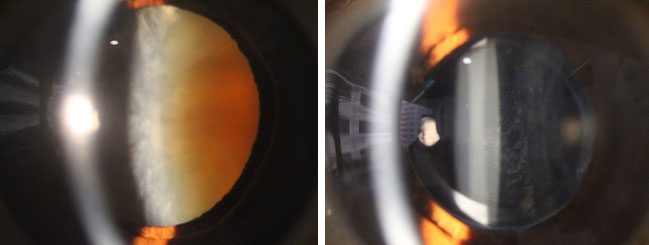

白內障手術前(左圖) 和後 (右圖)

白內障是指眼球內的晶體混濁,導致視力不清,情況就如一部相機的鏡頭受損,不能拍出清晰的照片。如要改善視力,必須把渾濁液晶體清除,再植入-片人工晶片,藉着個人化的人工晶片選擇,不但能改善視力,更能達致減少近視、遠視、散光,以致治療老化的效果。